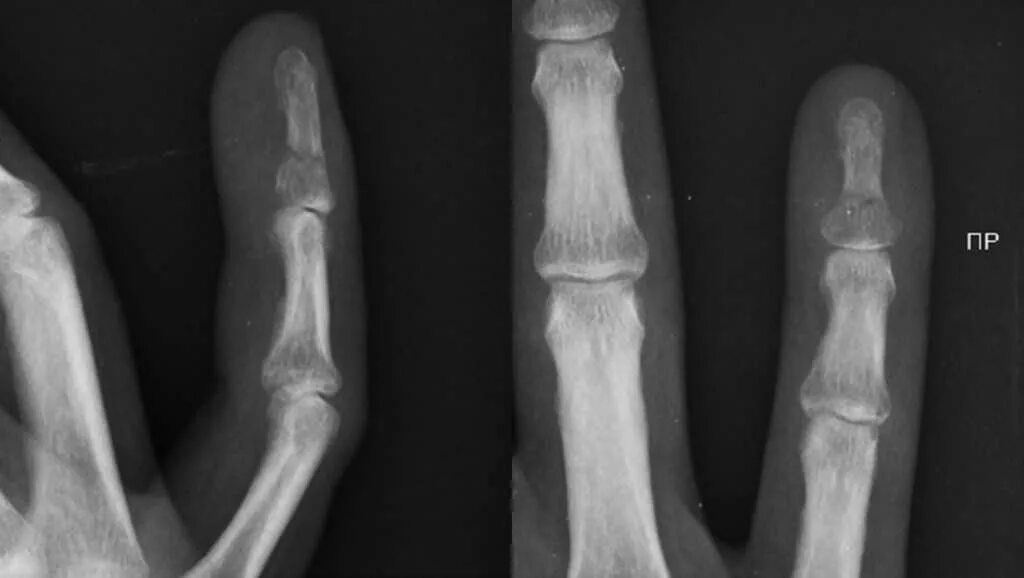

Перелом лучезапястного сустава мкб 10